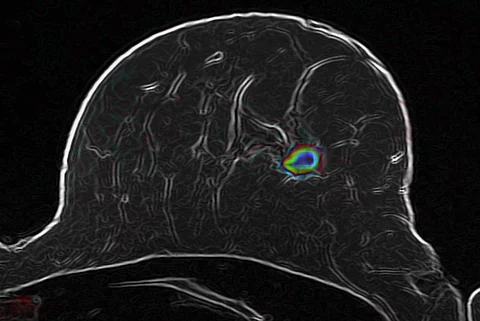

Bickelhaupt/DKFZ

BrustkrebsWie bildgebende Verfahren unnötige Biopsien vermeiden können

Die Diagnostik von Brustkrebs zu verbessern ist das erklärte Ziel eines Forscherteams vom Deutschen Krebsforschungszentrum in Heidelberg. Die Wissenschaftler kombinieren eine Weiterentwicklung der diffusionsgewichteten Magnetresonanztomografie mit intelligenten Bildanalyseverfahren, um bösartige Veränderungen im Gewebe aufzuspüren. Diese Methode…